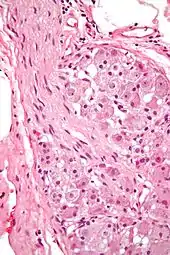

A ganglion cell is a cell found in a ganglion. Examples of ganglion cells include:

- Retinal ganglion cell (RGC) found in the ganglion cell layer of the retina

- Cells that reside in the adrenal medulla, where they are involved in the sympathetic nervous system's release of epinephrine and norepinephrine into the blood stream

- Cells of the sympathetic ganglia

- Cells of the parasympathetic ganglia

- Cells of the spiral ganglia